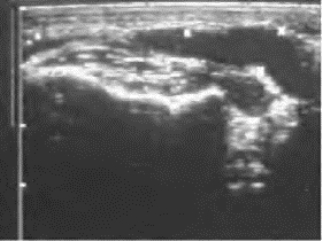

1.二维超声 炎症尚未局限时,病变区组织弥漫性增厚,边界不清;部分脓肿形成可见不规则的液性无回声区及部分低回声区;完全液化时为液性暗区,边界轮廓常欠清,外形呈梭形或扁片状居多。见图6-3。

图6-3 咬肌间隙感染声像图